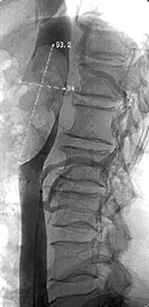

- Опухолевый тромбоз НПВ (рис. 11).

Рисунок 11. Кавограмма больного с опухолевым тромбом, достигающим диафрагмы